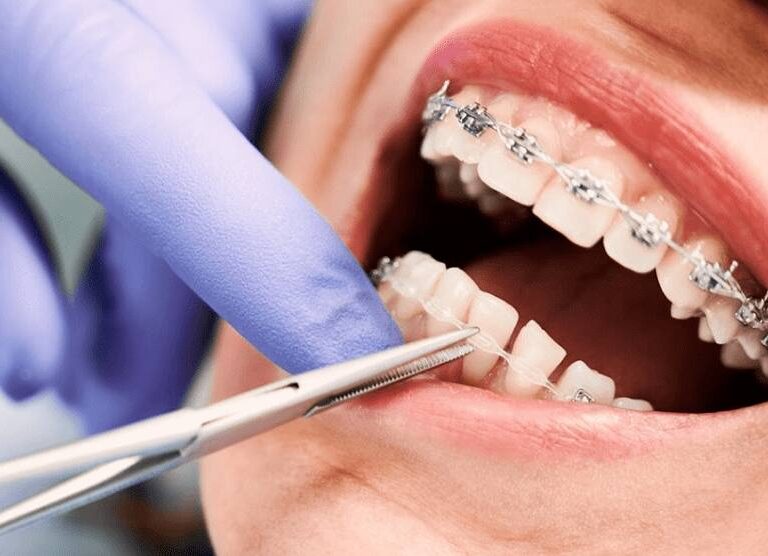

Necessity of a Microscope in Dentistry at DentalClinic24 – How Magnification and Visual Control Improve Treatment Precision

Precision in dentistry is determined not only by the clinician’s experience, but also by the level of visual control over the working field during treatment. Within the clinical approach of